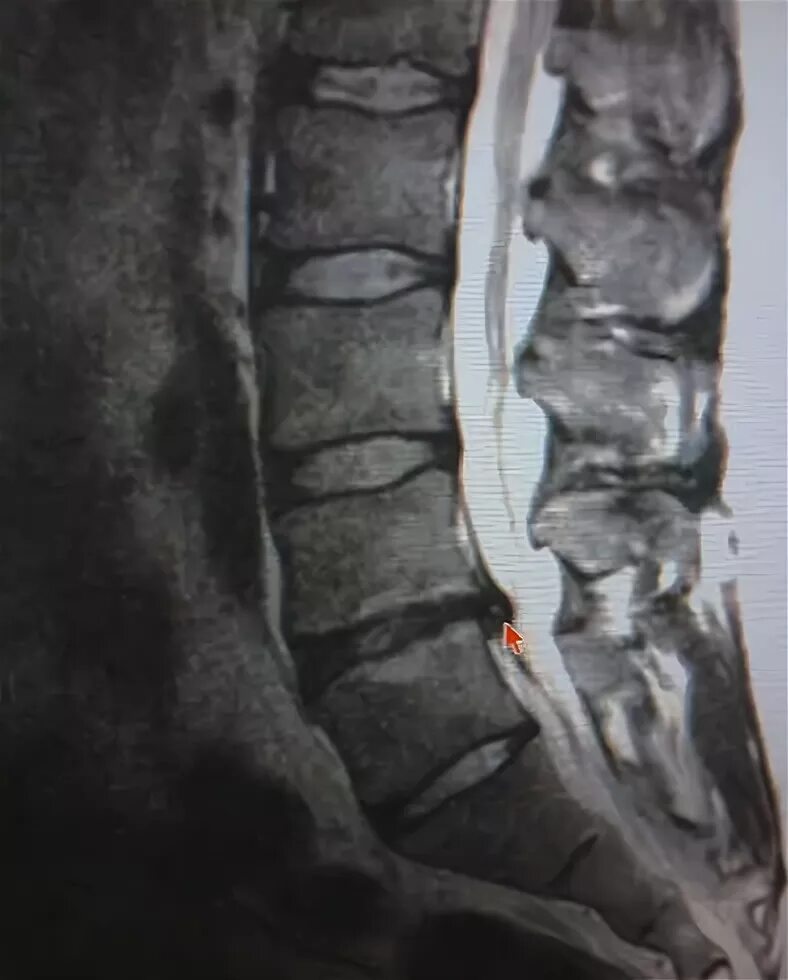

L5 s1 симптомы